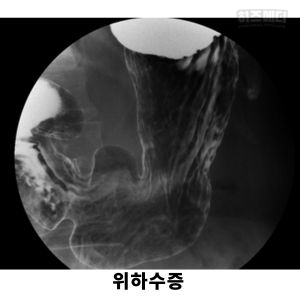

위장조영검사는 바륨이라는 인체에 해롭지 않은 조영제로 상부위장관(식도, 위, 십이지장)의 표면을 코팅하여 검사를 진행합니다. 다양한 자세에서 코팅된 표면을 방사선 기기로 촬영하고 분석하여 상부위장관의 병변을 찾아냅니다.

위하수는 위장이 배꼽 아래쪽 골반 근처까지 쳐져 있는 상태를 말합니다. 위장조영검사에서 서서 방사선 촬영을 했을 때, 위의 한 부분인 위각이 양쪽 골반의 상단 부분인 엉덩뼈능선(장골능)의 높이보다 아래쪽에 위치하면 위하수로 생각하게 됩니다.